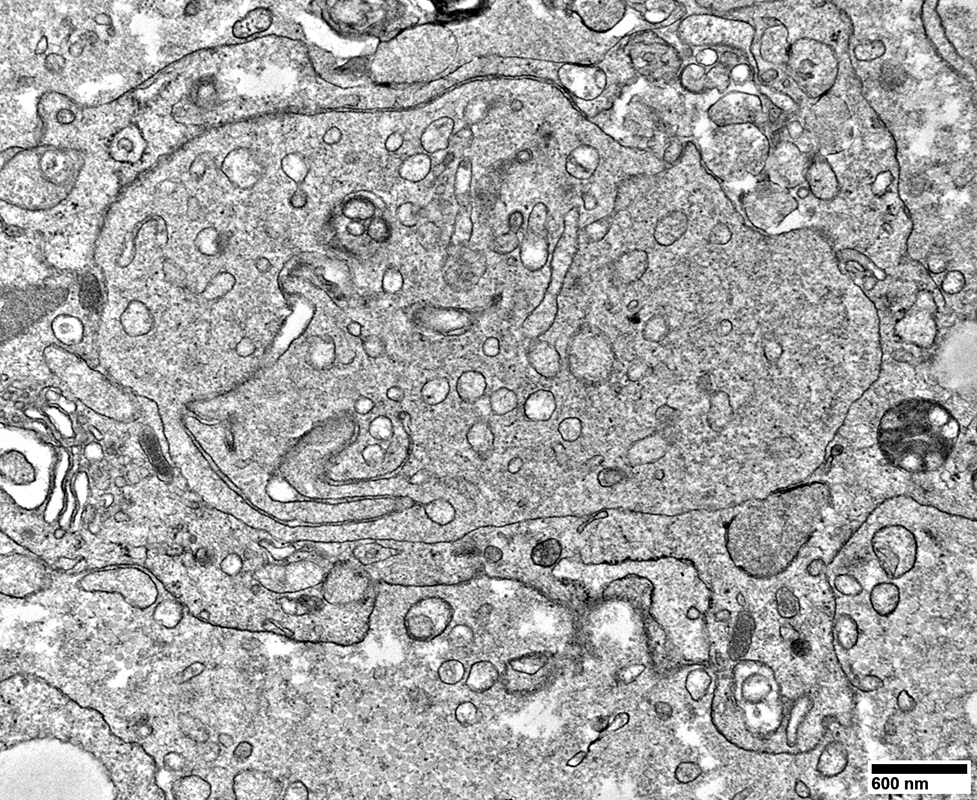

Axons surronded by multiple small Schwann cell processes

From: R Schmidt

Axons surronded by layers of Schwann cell processes